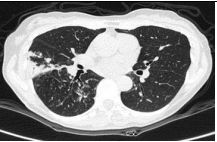

17. 50 y/o Female, Progressive dyspnea and cough for months.